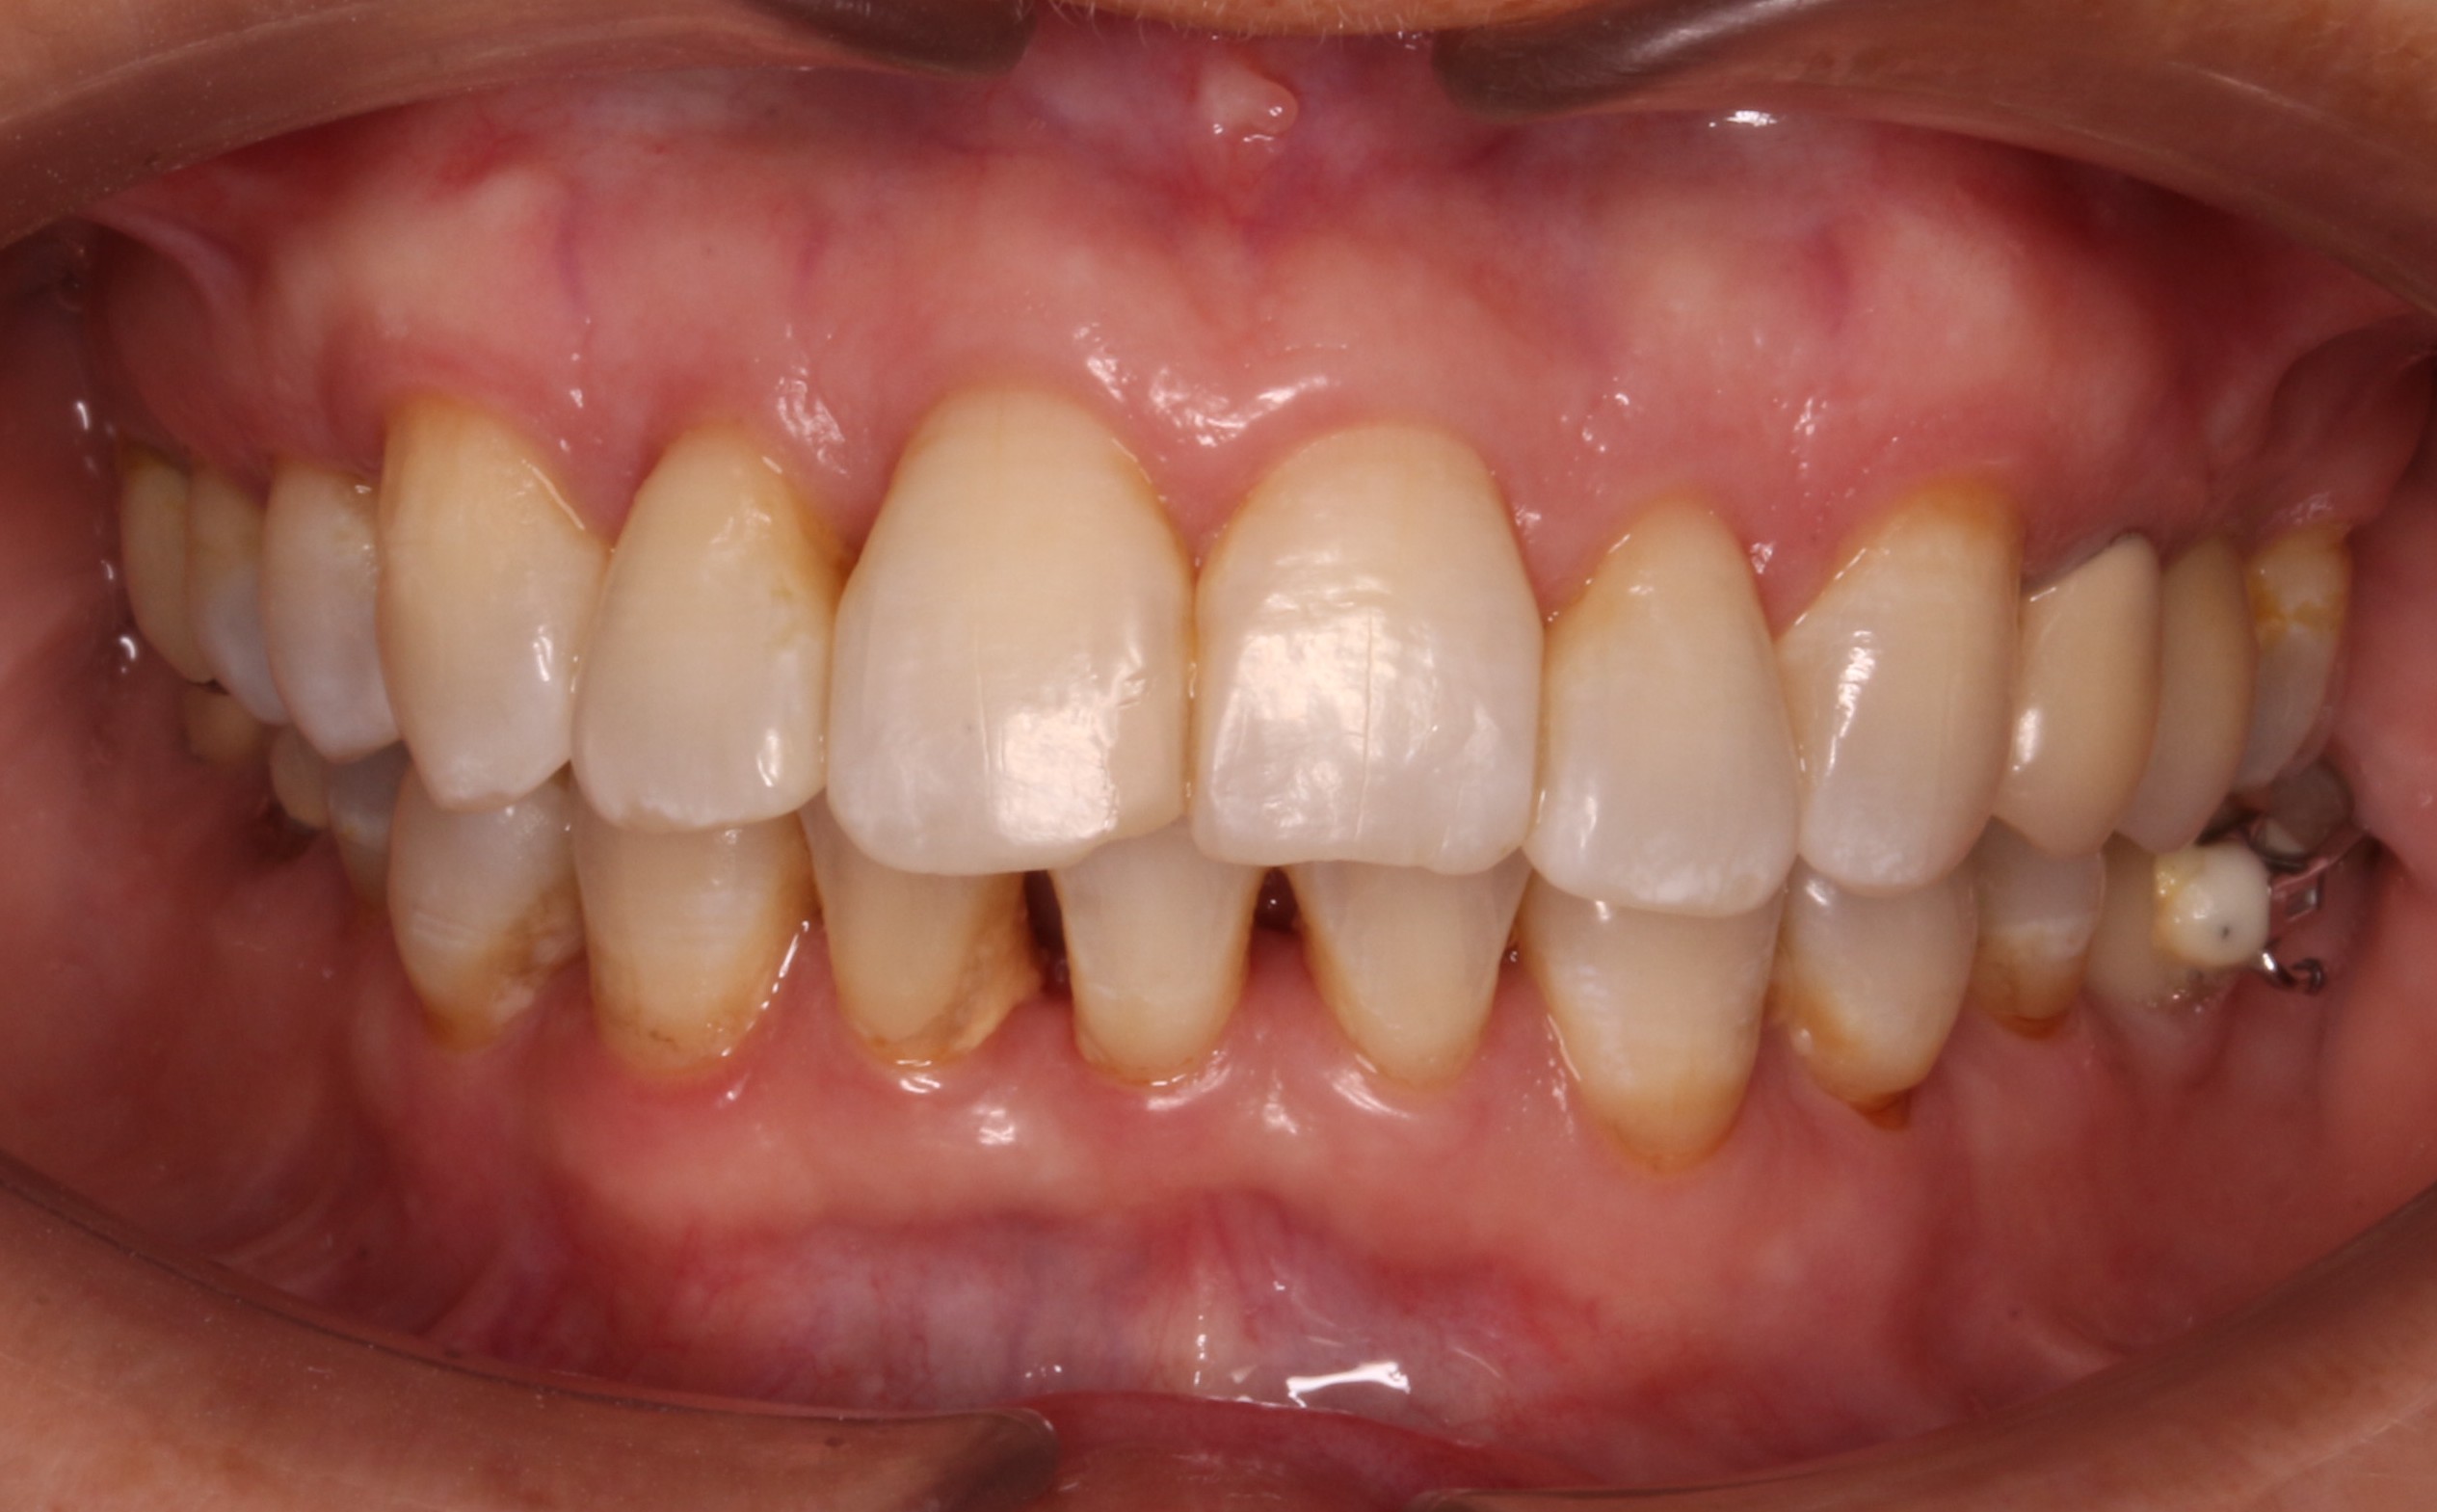

Alineadores + Brackets

Esta paciente de 30 años acudió a nuestra consulta con un objetivo muy especial: estaba a punto de casarse y deseaba mejorar la estética de su sonrisa en el menor tiempo posible. Para cumplir con sus expectativas, diseñamos un plan de tratamiento combinado: alineadores transparentes en el maxilar superior, para mantener la estética durante el proceso, y brackets metálicos en la arcada inferior, para acelerar los resultados. Esta estrategia nos permitió adaptarnos a sus necesidades y tiempos. El resultado fue una sonrisa radiante con la que celebró su gran día.